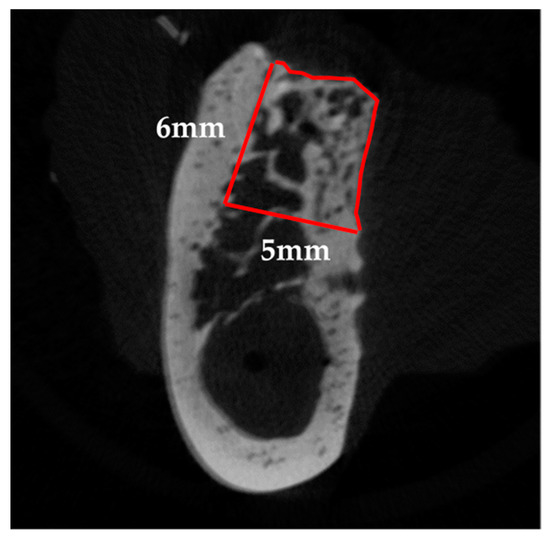

Local anesthesia using 2% lidocaine (Xylocaine, Dentsply Sirona Corp., Tokyo, Japan) was administered from the first mandibular premolar (P1) to the second mandibular molar (M2). Mucosal incisions were performed, one along the P1 to M2 cervical region, followed by vertical incisions at P1 and M2. The mucoperiosteal flap was elevated, and the second (P2), third (P3), and fourth premolar (P4), as well as the first molar (M1) were extracted. Subsequently, using a dental fissure burr (Osada portable unit “Daisy”, Osada Electric Industry Co., Ltd., Tokyo, Japan), a box-shaped defect (25-mm mesiodistal width; 6-mm depth; 5-mm depth from the buccoalveolar bone surface) was created while continuing irrigation with physiological saline (Figure 3a).

CTAn (ver. 1.15; Bruker Corp.) was used to perform 3D analysis, and to distinguish mineralized tissue, the Otsu algorithm was used to select a threshold of 659 mgHA/mL across all samples. First, the mid-section of the bone defect was determined on the 3D images by referring to the distance from the cervical portion of P1 and M2, and the center of the mental foramen to the edge of the bone defect measured during surgery, as well as the dental radiographs taken immediately after surgery. The two sections were subsequently identified as the mesio-distal limit of the bone defect, 12 mm away from the mid-section, mesially and distally. After identifying the border between the bone defect and the host bone in these sections, the range surrounded by the linear margin of the bone defect (6 mm in height with a 5-mm base) and perimeter of the newly formed bone was manually outlined as the region of interest (ROI). Furthermore, the volume interpolated between these ROIs was referred to as the volume of interest (Figure 4). Following that, tissue volume (TV), bone volume (BV), bone volume-to-tissue volume ratio (BV/TV ratio), and BMD were calculated within the bone defect as radiological morphometric indices [19]. Micro-CT analysis was performed as previously described [17,18].

Figure 4. Radiographic analysis. The red line represents the region of interest (ROI). On the sections, 12 mm away from the mid-section, both mesially and distally, the range surrounded by the linear margin of the bone defect (6-mm height, 5-mm base) and the perimeter of the newly formed bone was manually outlined after identifying the border between the bone defect and the host bone.